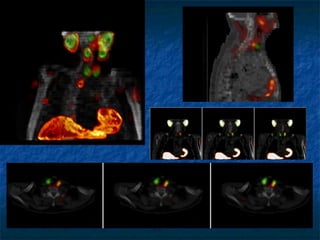

Animal

SPECT/CT